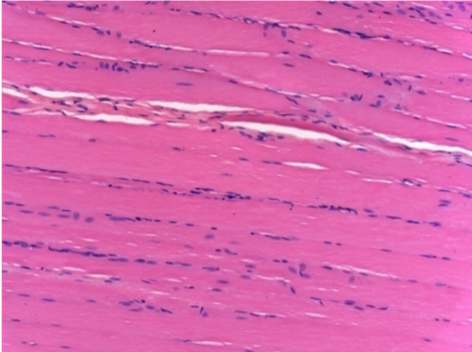

3 meses (D90) después de la inyección de Endopeel 0.1ml en el músculo pretibial derecho.

09